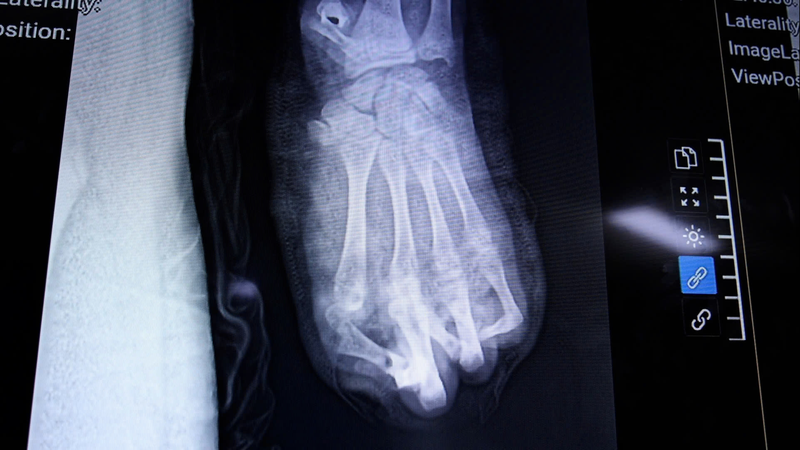

Toàn bộ vùng gan bàn tay và cổ tay bị dập nát nặng, khiến quá trình điều trị dự kiến kéo dài và phải trải qua nhiều cuộc phẫu thuật tiếp theo. Trong thời gian tới, người bệnh sẽ được che phủ các vùng hoại tử bằng vạt da. Sau vài tháng, nếu điều kiện cho phép, các bác sĩ dự kiến phẫu thuật chuyển ngón chân lên thay thế cho ngón tay cái đã mất.